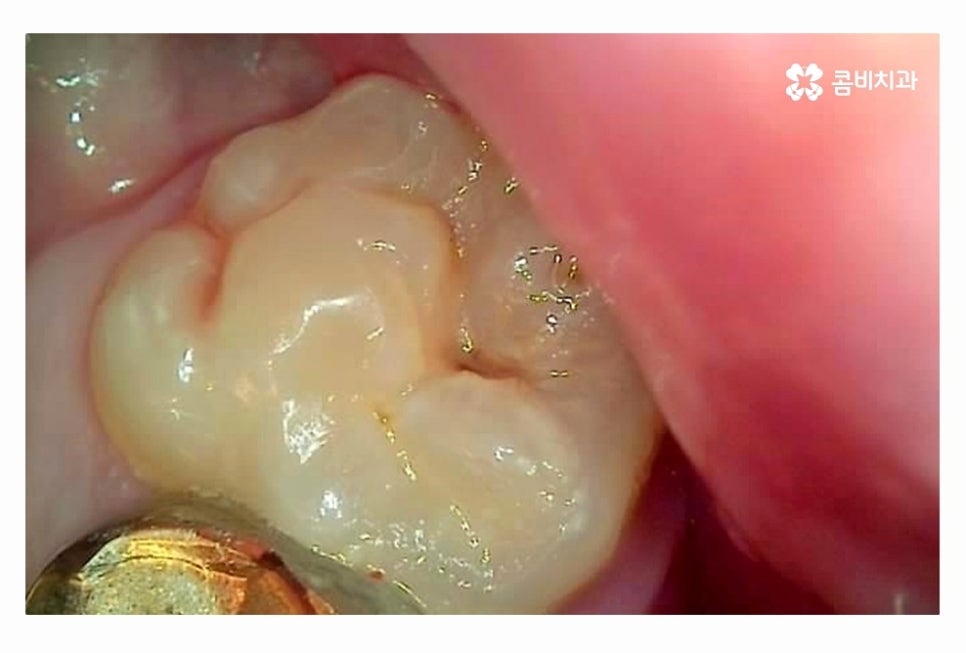

임플란트의 원리는 잇몸에 임플란트를 식립하고 골유착 과정을 통해서

단단하게 인공치근이 고정이 되고 보철물을 연결하여

자연치아의 기능 거의 대부분을 회복할 수 있는데요.

20대임플란트 치료를 하시는 분들의 경우 충치, 사고 등으로

치아를 잃게 되는 경우가 많기 때문에 치료는 크게 어려운 경우는 많지 않지만